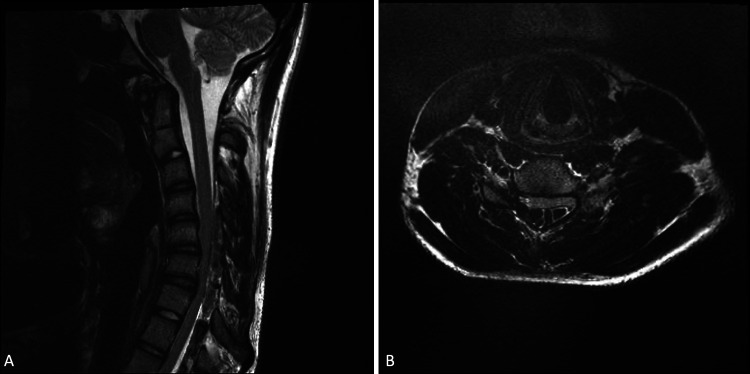

FIG. 2.

A: Flexion sagittal T2-weighted MRI showing extreme compression of the C4-C7 region. B: Flexion axial MRI showing compression of C4-C7 region.

Physical examination revealed significant weakness in his right upper extremity as well as severe atrophy of his right hand and forearm. The patient was full strength (5/5) in his proximal right upper extremity, including deltoid and biceps, decreasing distally to 2/5 in his intrinsic hand muscles. Pectoralis asymmetry was also noted, with slightly smaller musculature on the right side. Patellar reflexes were increased bilaterally. No fasciculations were detected, and the patient did not report any upper extremity pain. Additionally, no family history of neuromuscular or peripheral nerve disorders was reported. The patient saw several providers, but no diagnosis was reached because his static cervical spine MRI appeared normal (Fig. 1). Electromyographic examination revealed marked low amplitudes of the right median and ulnar muscle action potentials with normal sensory nerve potentials, indicative of a chronic neurogenic process. Based on clinical suspicion, a flexion MRI was performed, and it revealed significant anterior displacement of the thecal sac, effacement of the subarachnoid space from C5 to C7, and engorgement of the posterior, epidural veins. A diagnosis of HD was confirmed (Fig. 2A and B).